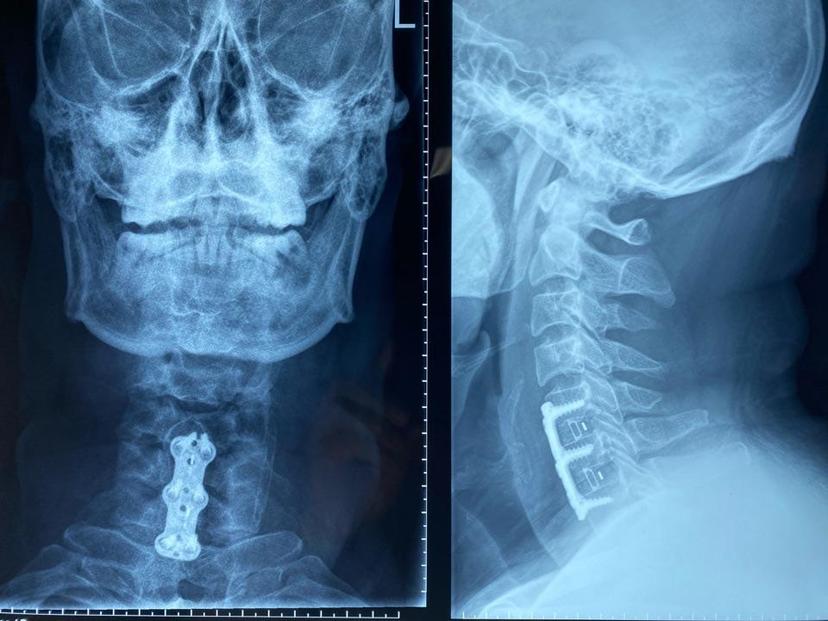

患者颈部疼痛,上肢酸痛麻木,行走不稳,经过颈椎磁共振+颈椎CT检查,颈6-7椎间盘脱出导致椎管狭窄,颈5-6层面后纵韧带骨化及大量骨赘,均采用前路单间隙减压微创术式,避免了椎体切除,术中出血少、手术时间短、术后三天出院,不适症状完全消失!磁共振显示颈6-7椎间盘脱出占满整个椎管空间,脊髓完全受压

采用颈前路微创手术致压物完全去除,位置良好,术后不适症状完全消失,三天康复出院